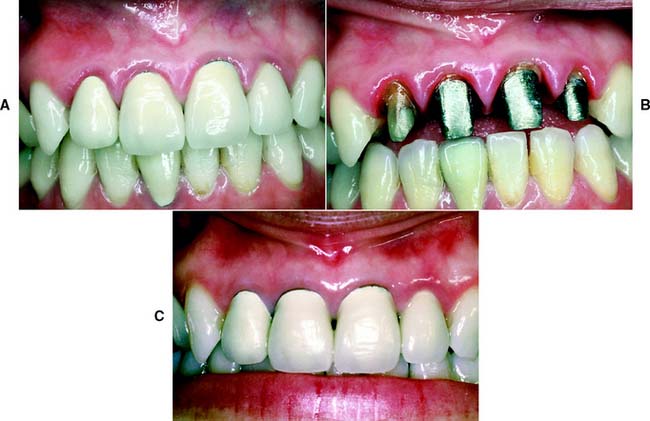

Gingival inflammation is commonly associated with crowns and fixed dental prosthetic abutments that have excessive axial contours, probably because it is more difficult for the patient to maintain plaque control around the gingival margin24 (Fig. 7-15). A tooth preparation must provide sufficient space for the development of good axial contours. This enables the junction between the restoration and the tooth to be smooth and free of any ledges or abrupt changes in direction.

Fig. 7-15 A, Unhealthy gingival tissue resulting from overcontoured restorations. B, The tooth preparations are underreduced; C, Once the restorations are recontoured, gingival health returns.

Under most circumstances, a crown should duplicate the contours and profile of the original tooth (unless the restoration is needed to correct a malformed or malpositioned tooth). If an error is made, a slightly undercontoured flat restoration is better because it is easier to keep free of plaque; however, increasing proximal contour on anterior crowns to maintain the interproximal papilla25 (see Chapter 5) may be beneficial. Sufficient tooth structure must be removed to allow the development of correctly formed axial contours (Fig. 7-16), particularly in the interproximal and furcation areas of posterior teeth, where periodontal disease often progresses with serious consequences.